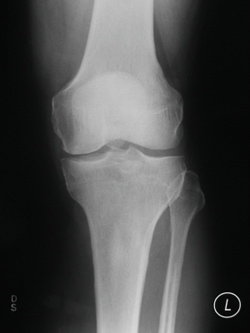

| Osteoarthritic Knee |

Normal Knee |

The cartilage is a padding that absorbs stress. Usually the pain early on is due to inflammation. In the later stages, when the cartilage is worn away, most of the pain comes from the mechanical friction of raw bones rubbing on to each other.